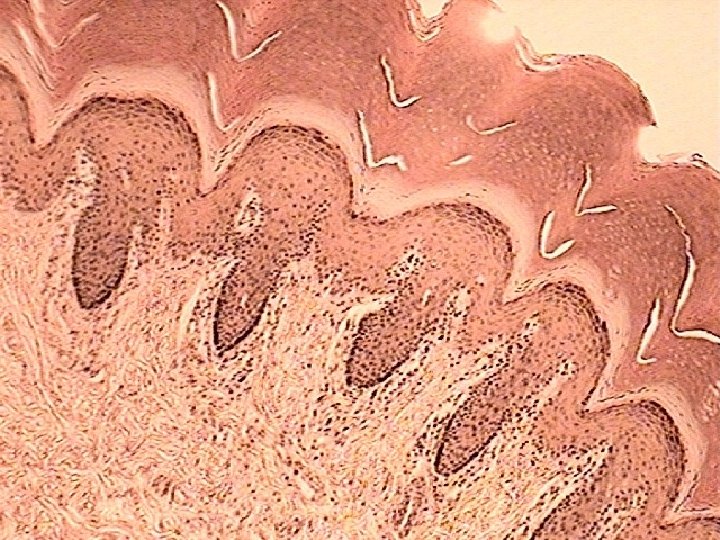

Layers of the Dermis • Reticular region: consists of dense irregular CT Contain most of the accessory Structures 3. Papillary Region: Consist of areolar Tissue 4. Dermal Papilla: Fingerlike projections that greatly increase surface area 4 3 1 2

Special Sensory apparatus of the dermis Meissner’s Corpuscles: • Present in dermal papilla • Specialized sensory neuron nerve endings • Respond to touch • Most numerous in thick or non-hairy skin of the palmar and plantar surfaces